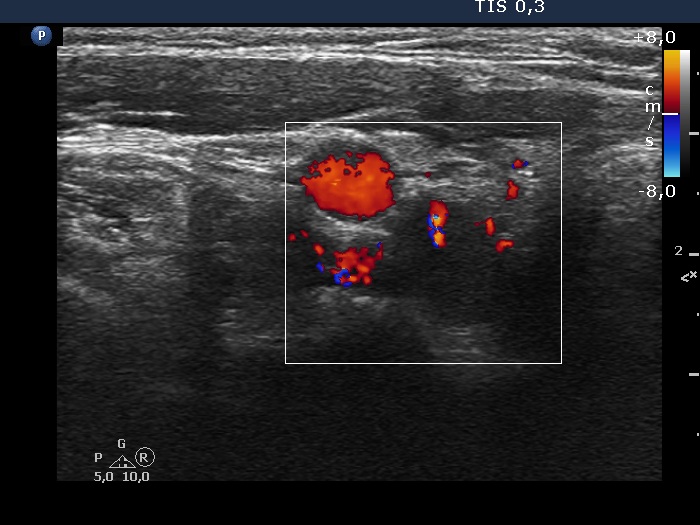

Right lobe, longitudinal scan

Lower part of the right lobe, transverse view, color Doppler mode. The lesion has intralesional vascularity.